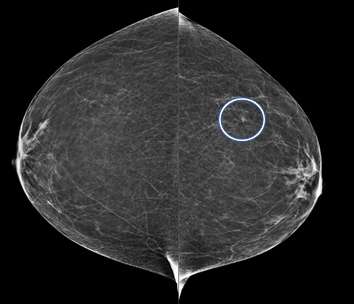

Focal Asymmetry:

A focal asymmetry is a finding seen on two projections3. Focal asymmetries that have been evaluated without suspicious features but persist are likely benign and can be managed with 6-month short-term imaging follow up.